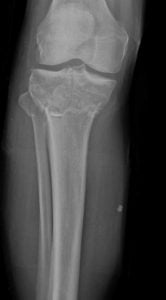

Tibial plateau fracture recovery blog. Tibial Plateau Fracture Recovery Blog. Looking at the above photo always makes me cringe when I think back to that fateful dayMay 20th 2017 Yes folks somehow I managed to acquire a tibial plateau fracture TPF This particular fracture makes up only 1 of all fractures. Just let that sink in for a bit.

These fractures are usually visible on a simple x-ray. Tibial plateau fractures requiring surgery are severe injuries of the lower extremity. Tibial plateau fractures have an impact not only on physically demanding jobs but notably on general professional life too.